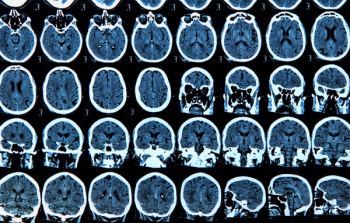

Utilizing susceptibility-weighted magnetic resonance imaging (MRI) in a study involving over 20,700 people, researchers found that drinking more than seven units (56 grams) of alcohol a week led to a higher accumulation of brain iron, which can trigger cognitive decline.